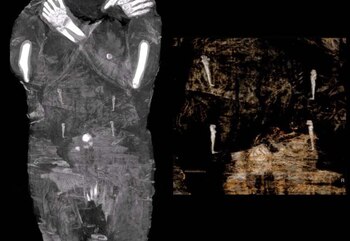

“Mi esposo Stanislaw, egiptólogo, y yo, al examinar las imágenes radiográficas, notamos en el útero de la mujer fallecida un cuadro familiar para padres de tres hijos: ¡un pequeño pie!”, señaló ante periodistas Marzena Ozarek-Szilke, antropóloga y arqueóloga de la universidad de Varsovia. “No sabemos por qué no sacaron al feto del útero de la difunta durante su momificación”, señaló Wojciech Ejsmond, de la Academia de Ciencias polaca, que también participa en el proyecto.

La momia no ha sido abierta, pero una de las radiografías muestra que la mujer tenía el pelo largo y rizado, que le llegaba hasta los hombros. Calculan que la mujer tenía entre 20 y 30 años al morir y que por el tamaño del cráneo del bebé, estaba entre la 26ta y 28va semana de embarazo.

“Nos llevamos la primera sorpresa al ver que no tenía pene, y que en cambio tenía senos y pelo largo. Después descubrimos que era una mujer embarazada”, dijo Ozarek-Szilke a The Associated Press. “Cuando vimos el pequeño pie y la pequeña mano (del feto) quedamos atónitos”.